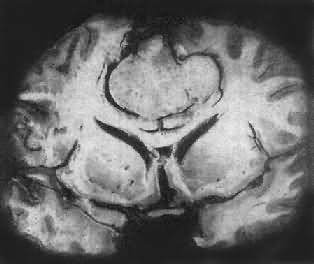

肉眼观,肿瘤为数厘米的结节至巨大块状。分化较好的肿瘤,境界不清;而分化程度较低的肿瘤则境界分明。瘤体灰白色。质地视肿瘤内胶质纤维多少而异,或硬、或软、或呈胶冻状外观,并可形成大小不等的囊腔。由于肿瘤的生长、占位和邻近脑细胞的肿胀,脑的原有结构因受挤压而扭曲变形(图16-23)。

图16-23 星形胶质细胞瘤

左大脑半球肿胀,肿瘤边界不清,部分呈胶冻状